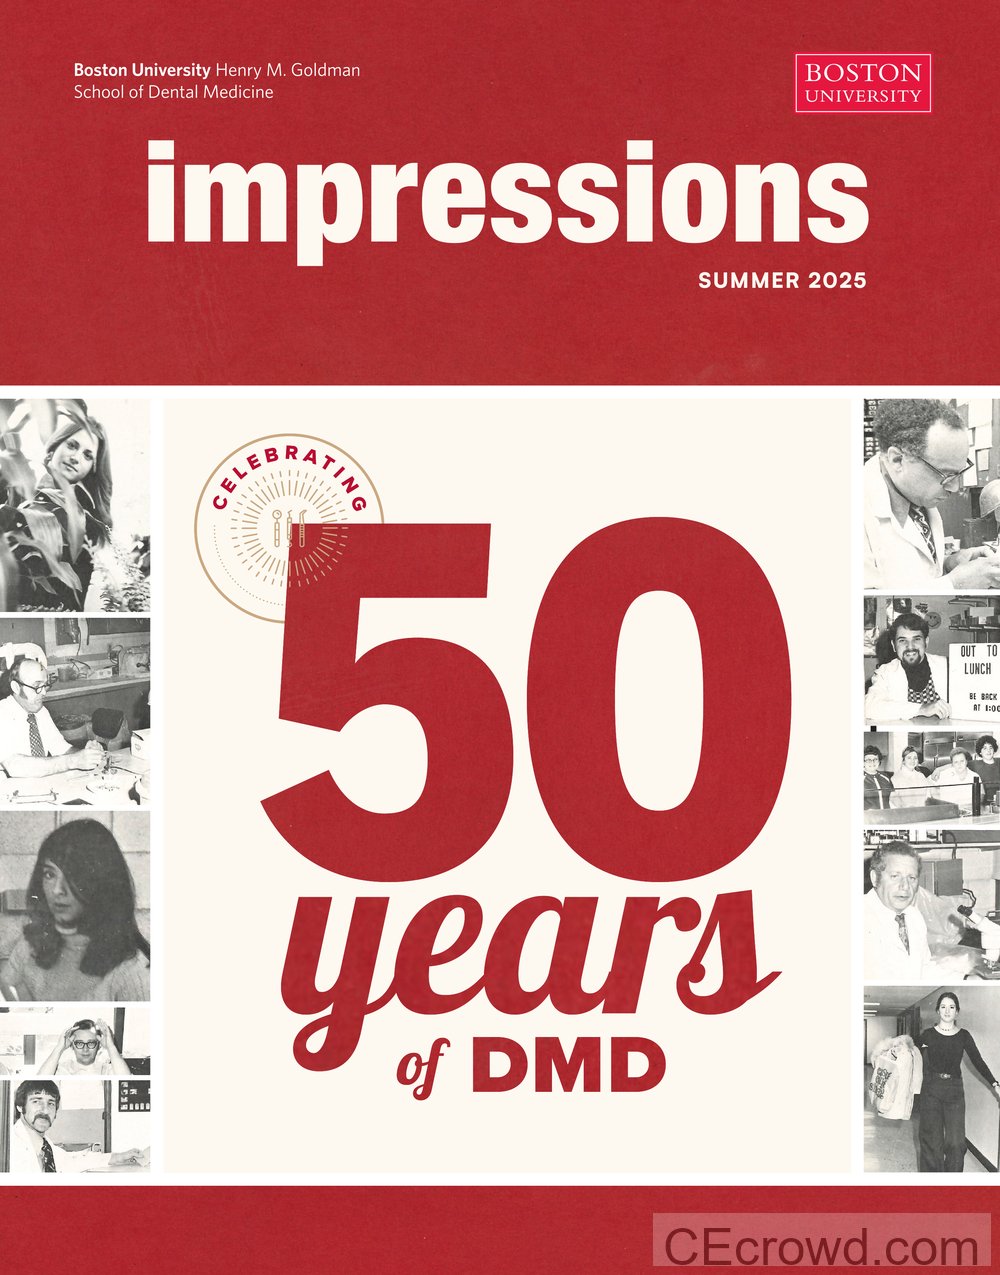

Foundations in Physiologic-Based Dentistry for Complex Restorations

Hands-on course teaching physiologic-based dentistry to diagnose and treat complex cases, including TMD, bruxism, airway relationships, and restorative strategies to improve patient outcomes.